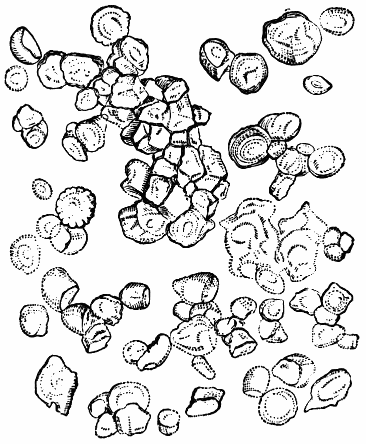

IPECACUAN′HA. Syn. (Ipecacuanha, L.; Ipecacuhan, E., B. P.) Radix ipecacuanhæ, Ipecacuanha (Ph. L. E. & D.), L. The dried root of Cephaëlis Ipecacuanha, or the true ipecacuanha plant, one of the Cinchonaceæ. “Ashy coloured, tortuous, very much cracked, and marked in rings with deep fissures, having an acrid, aromatic, bitterish taste.” (Ph. L.) It occurs in pieces 3 or 4 inches long, and about the size of a writing quill.—Dose. As an emetic, 10 to 20 gr., assisted by the copious use of warm water; as a nauseant, 1 to 3 gr.; as an expectorant and sudorific, 1⁄2 to 1 gr. It is undoubtedly the safest and most useful medicine of its class. It has recently been highly recommended in dyspepsia, combined with other bitters or aperients. Almond meal is sometimes used as an adulterant in ipecacuanha powder.